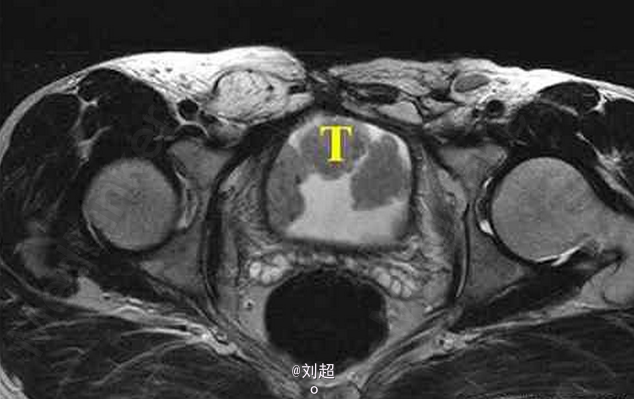

患者尿频、尿急、尿痛,有肉眼可见血尿 辅查MRI,平扫见膀胱侧壁和前上壁呈菜花样突入腔内,T1WI呈低信号,T2WI呈稍高信号,增强后肿块明显强化

膀胱移行细胞癌 处理:手术配合放疗、化疗